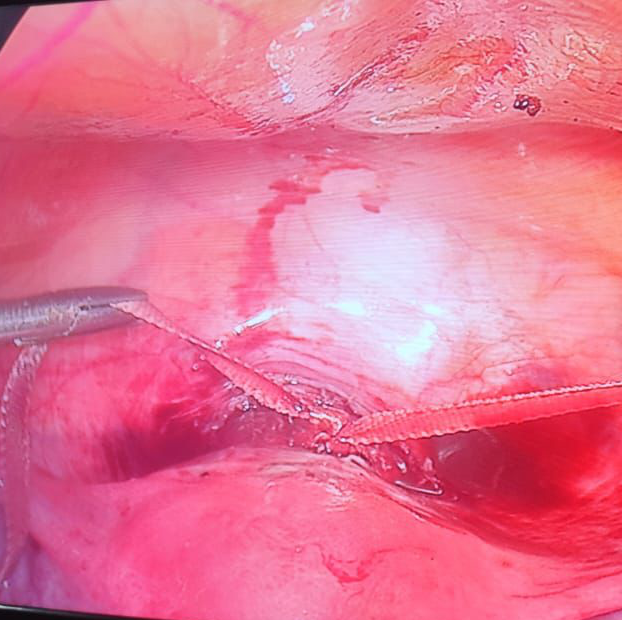

Laparoscopic cerclage or Cervical stitch now offered at Delight women’s hospital. Cervical stitch is needed for women who have painless miscarriage or whose cervix is short on Sonography. Laparoscopic route of surgery offers best chance for the women to carry a successful pregnancy till baby grows to a proper size. If you are suffering from Multiple miscarriages , please reach out to us and experience expert treatment for a successful pregnancy